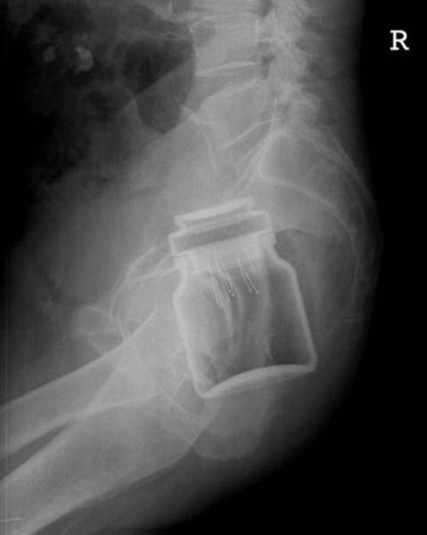

Предметы, которые не очень хочется видеть внутри себя

Под рентгеновскими лучами порой видны не только внутренние органы и кости, но и инородные тела, попавшие в организм

Истории попадания этих предметов в организм могут быть самыми невероятными и запутанными, но больше всего медиков интересует процесс их извлечения, впрочем, в этом заинтересованы и сами пациенты, допустившие нечто подобное со своим телом.